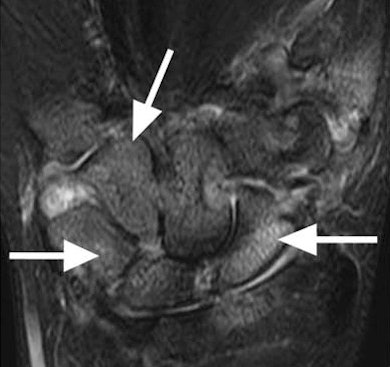

| Images show bone marrow edema in 31-year-old woman with rheumatoid arthritis. Extremity MRI (above) and conventional MRI (below) both show extensive and comparable edematous changes throughout the carpal bones (arrows). Images courtesy of Radiology. |

The readers' image analyses demonstrated "almost perfect agreement between the results on the extremity and conventional MR systems for both readers with regard to bone erosion, synovitis, bone marrow edema, and total scores," the study noted. "Intraclass correlation coefficients were highest for erosion, bone marrow edema, and total scores, but even the synovitis scores demonstrated high agreement between the two systems."

On the basis of those observations, the researchers concluded that "inflammatory and destructive changes in rheumatoid arthritis are equally well demonstrated with the 1T extremity MR system as with the conventional 1.5T system."

They also added that the 1-tesla extremity system demonstrated "excellent correlation with the 1.5T conventional system, with respect to demonstration of bone marrow edema and synovitis, features that have been problematic for 0.2T extremity systems."